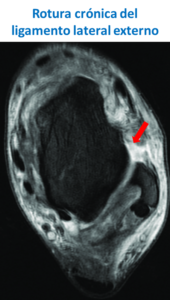

Para diagnosticar adecuadamente esta lesión además de explorar adecuadamente al paciente debemos realizar radiografías de tobillo y una resonancia magnética, que nos dará datos de que ligamentos están dañados y si existen lesiones asociadas.